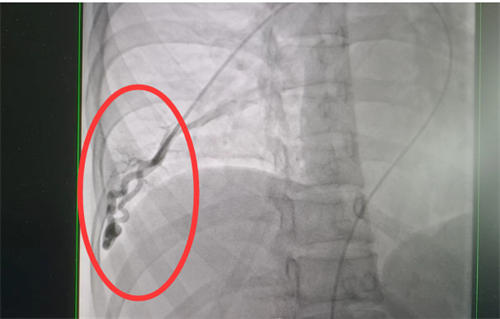

目前治疗肺动静脉瘘的方法有两种—介入手术及外科切除,可根据患者具体情况选择合适干预方式。通过积极处理,梁瑶脑梗症状得到控制,随后转入香港马会app外周血管介入科进行介入手术治疗。此类手术难度大,风险高,经科室团队仔细讨论,定下最佳方案,为患者顺利实施了肺动静脉瘘封堵术,手术全程4小时,术后平稳回到病房。术后复查肺动静脉瘘已消失不见,经过后续的对症治疗和护理,梁瑶恢复良好,于5月上旬出院。

术前肺动静脉瘘造影